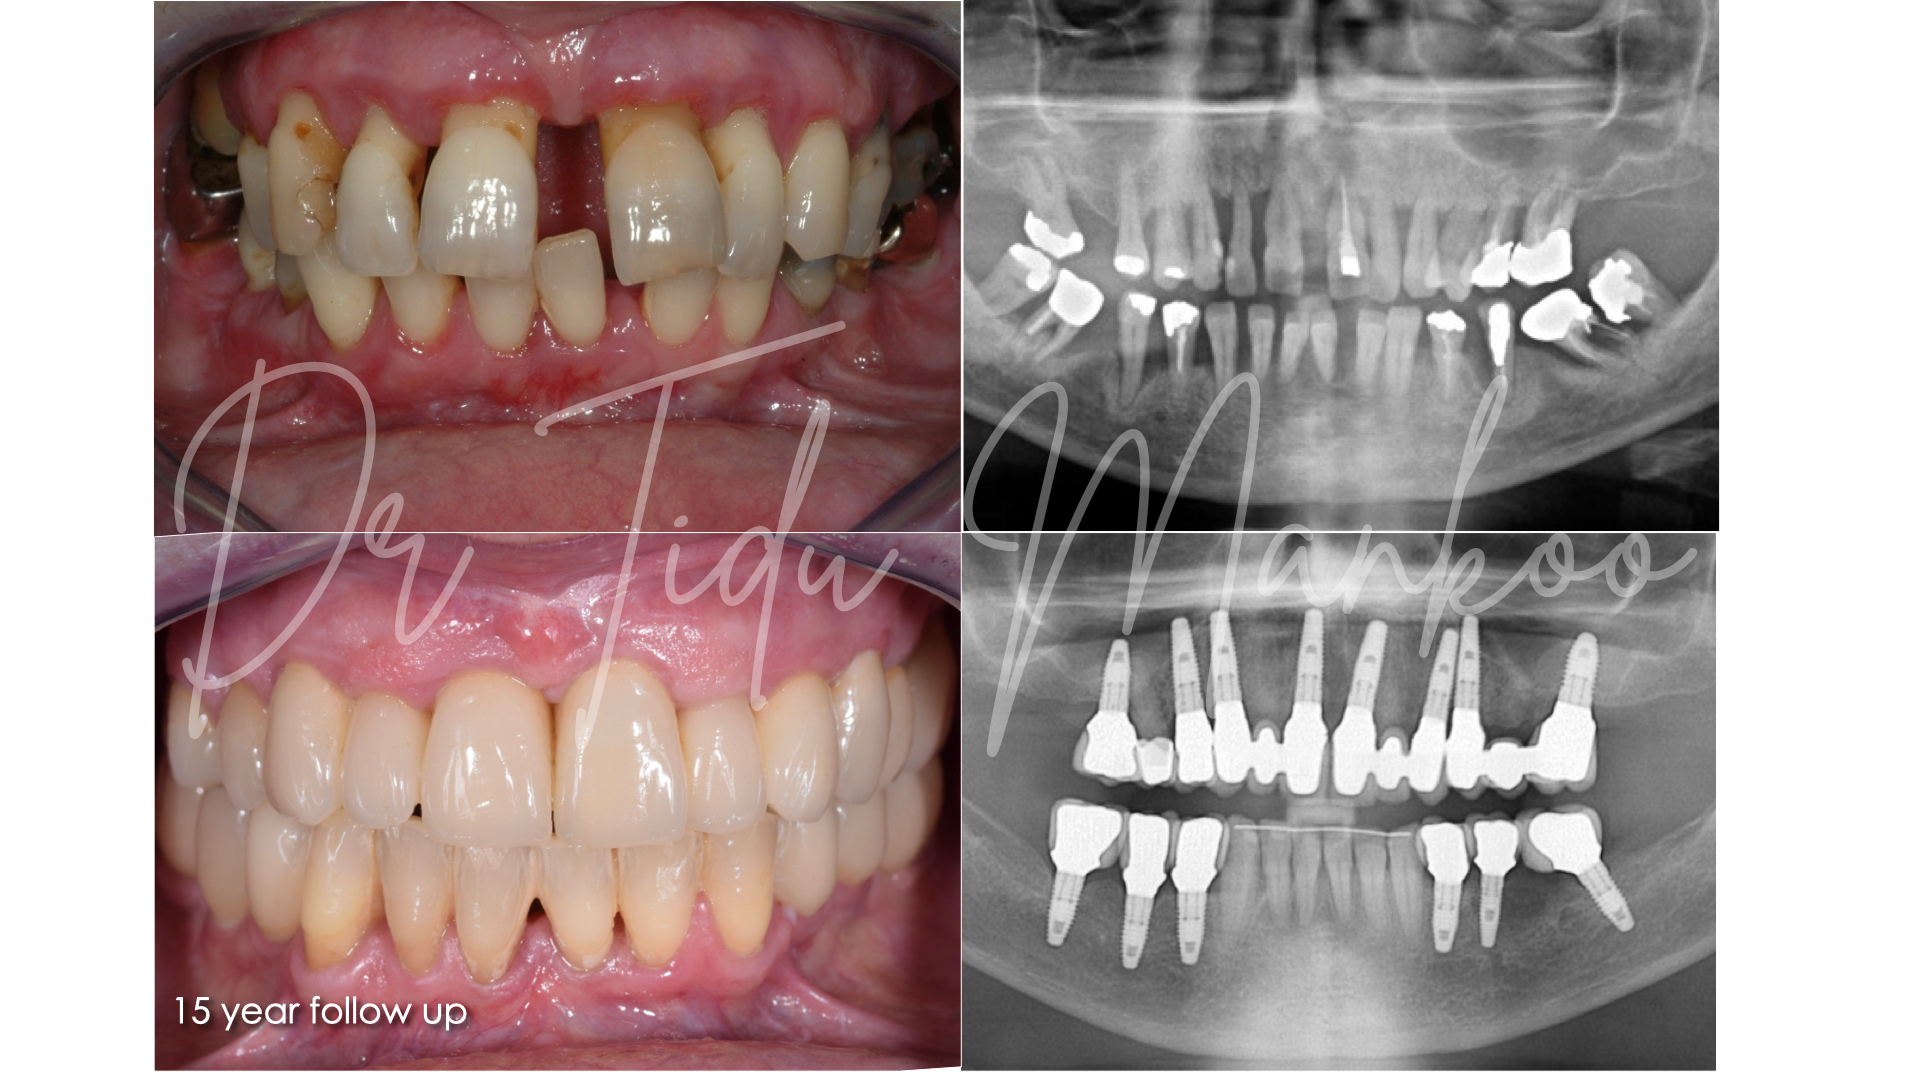

Participants have the fantastic opportunity to learn from a world renowned master clinician of outstanding expertise and experience. This course will outline the contemporary surgical and prosthetic concepts in management of teeth and implants with a view to achieving optimum long-term aesthetics, durability and stability. The emphasis will be on the clinical management and an understanding and application of the biological factors that influence our treatment outcomes. Management of bone, soft tissue and prosthetics contours and materials all play a key part in the aesthetic outcome and long-term stability of soft tissue aesthetics.

Interdisciplinary management of failed implants, severe alveolar defects and periodontally compromised teeth in the aesthetic zone:

• Failed implants and/or grafts and management of complex defects in the aesthetic zone Aesthetic management of periodontally compromised teeth

• Understand the surgical and prosthetic keys to long-term success with implants in the aesthetic zone

• Learn the current concepts in muco-gingival surgery and ‘pink’ aesthetics on teeth and implants to achieve the optimum long term results

• Gain an understanding of the biology of the peri-implant tissues and comprehend the behaviour of the bone & soft tissues in edentulous sites, post extraction sites and around dental implants

• Interdisciplinary management of severe alveolar defects, failed implants and periodontally compromised teeth in the aesthetic zone